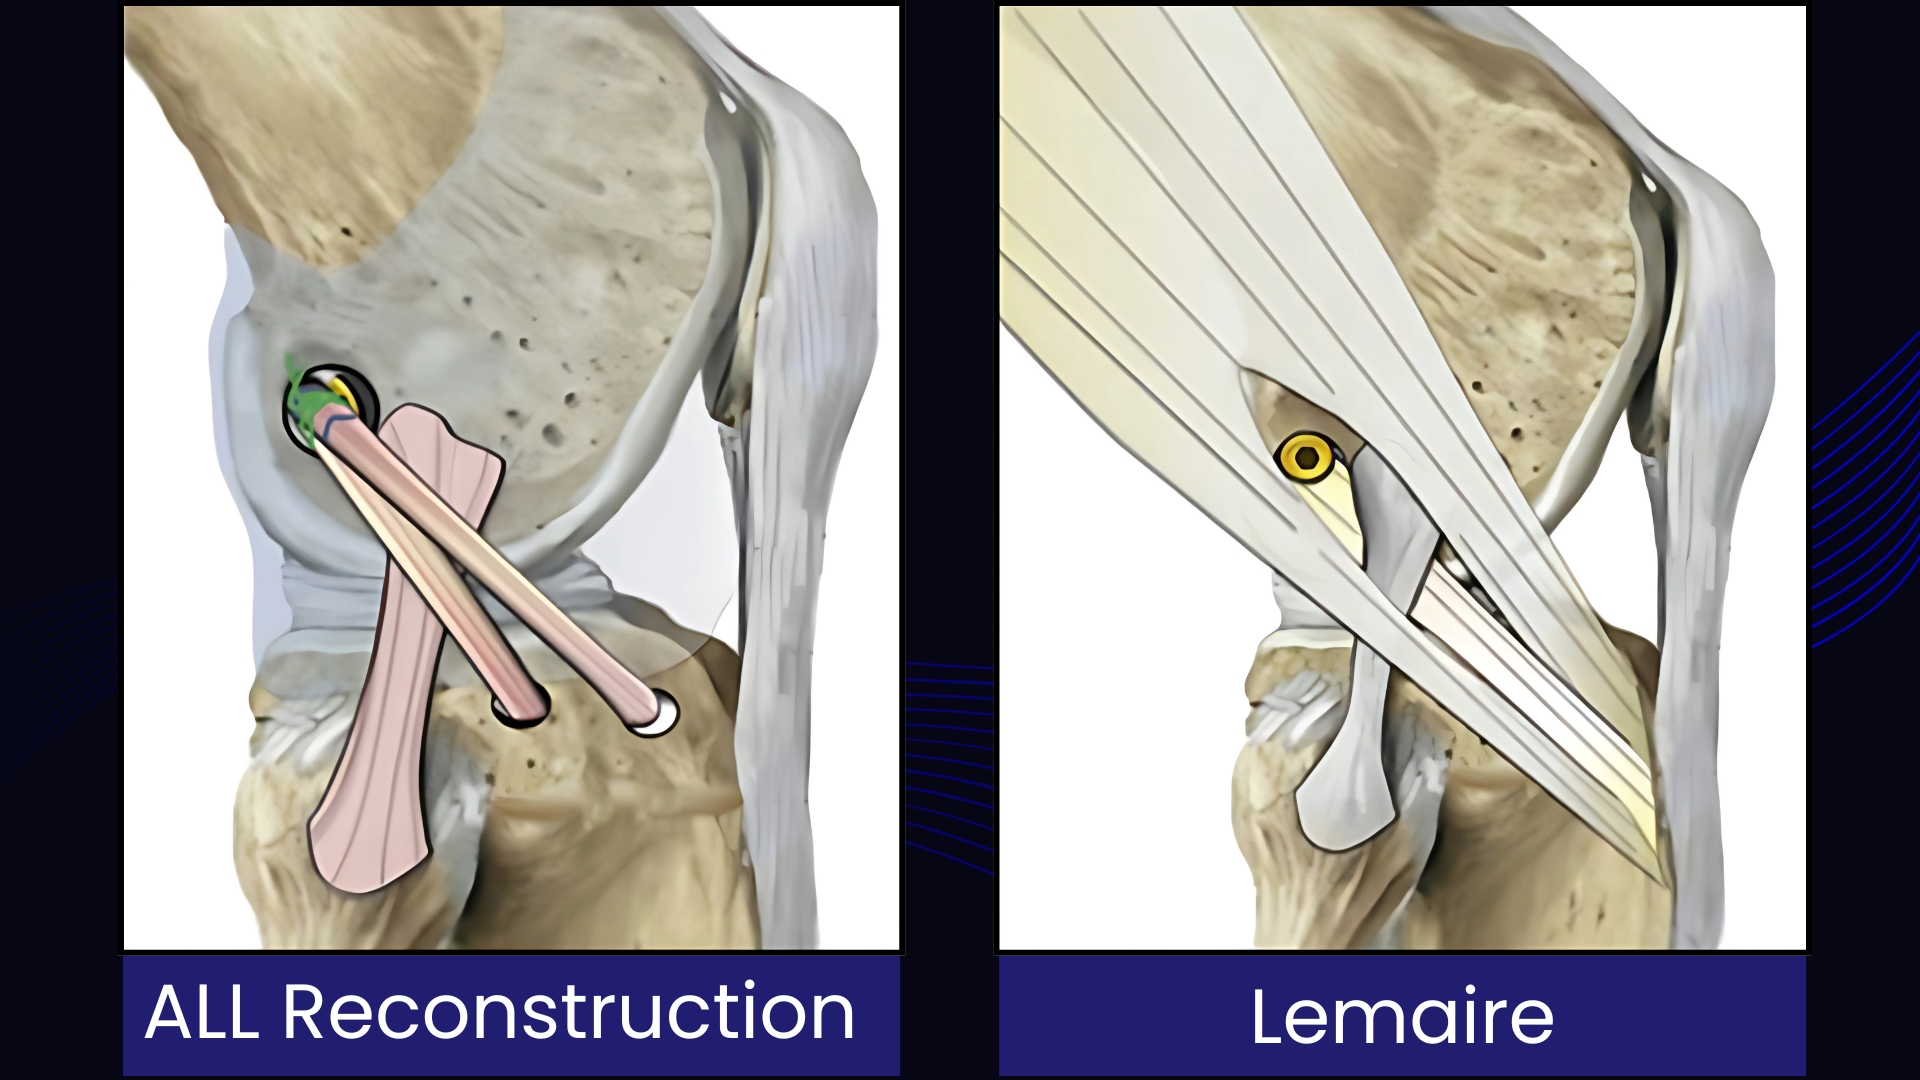

- Modified Lemaire ITB Tenodesis

- Anterolateral Ligament (ALL) Reconstruction

| Technique | Modified Lemaire ITB Tenodesis | ALL Reconstruction | Onlay ALL Reconstruction |

| Graft Source | Iliotibial Band (ITB) | Gracilis/ITB | Gracilis/ITB |

| Fixation | Fixation to bone surface (tenodesis) | Full bone tunnel | Shallow socket (onlay) |

| Anatomical Accuracy | Non-anatomic (functional restraint) | Anatomical | Anatomical (simplified) |

| Fixation Method | Distal attachment to bone, proximal end fixed with staple/screw/anchor. | Proximal and distal ends fixed within bone tunnels. | Proximal end fixed to the surface of the bone with anchors/screws; distal end may be in a tunnel. |

| Primary Advantage | Proven, effective, and technically simpler. Avoids the need for a separate free graft. | Aims for a more precise anatomical reconstruction. | Avoids tunnel convergence with the ACL graft, a major technical benefit. |

| Tunnel Convergence Risk | Minimal | Higher | Minimal |

| Key Limitation | Risk of over-constraint | Risk of tunnel convergence | Graft specificity, technical complexity |

| Ideal Use Case | Primary & revision cases, high-grade pivot shift | Surgeons prioritizing anatomy, primary cases | Revision surgery, multi-ligament injuries, narrow femurs |

- Modified Lemaire ITB Tenodesis remains a time-tested, effective option, particularly in young athletes and revision settings.

- ALL Reconstruction represents a precise, anatomical solution, restoring native biomechanics while minimizing over-constraint.